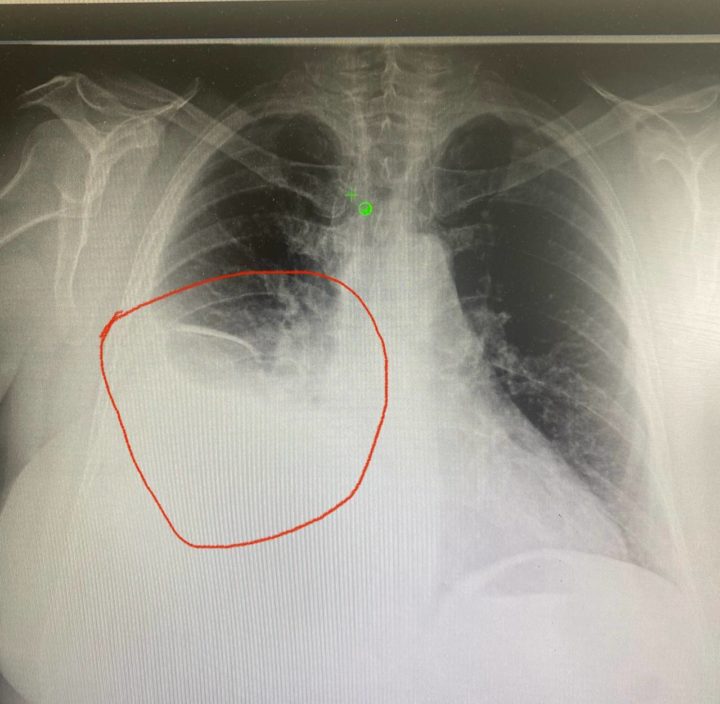

В итоге пенсионерку доставили в районную больницу, где хирург подготовил пациентку к дренированию плевральной полости — процедуре, при которой между двумя ребрами сделают прокол, и жидкость через трубку начнет стекать в специальный мешок.

— Пару недель назад можно было обойтись курсом антибиотиков, — отметил медик.